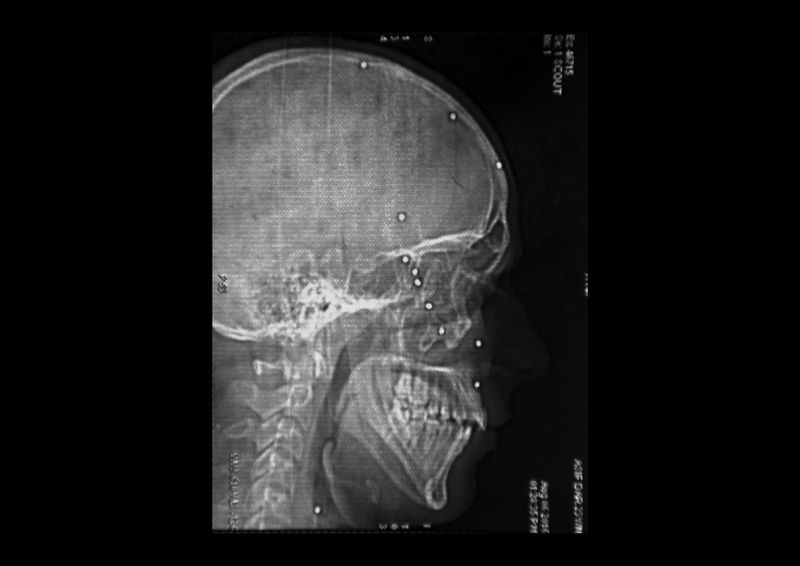

Amir Kabir Beigh, 26 years old, Baramulla. “In September 2010 i was going to buy some medicine for my mother by evening time when a group of security forces fired at me near the bridge of the old town. There had been clashes throughout the day but it was calm at that time. I was alone on the street so only after some minutes somebody found me and took me to the hospital. I have gone through a lot of surgeries all over India but i am still completely blind”. Amir is the first pellet victim of Kashmir, he received hundreds of iron balls on his body.